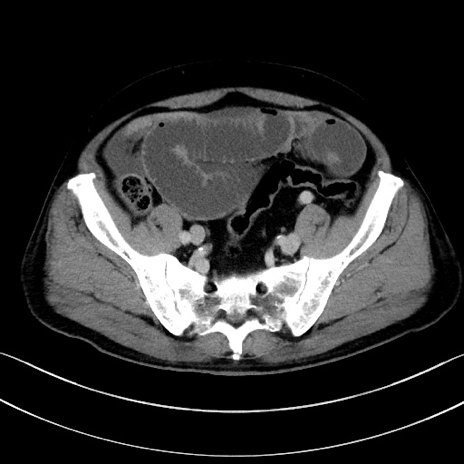

症例15(横断像)

【症例】70歳代男性

【主訴】腹痛

【現病歴】今朝から腹痛あり。全体的に痛い。特に左上の方。排ガスが今日はない。冷や汗が出る。

【既往歴】直腸癌術後

【身体所見】左側腹部〜上腹部に圧痛あり。腹膜刺激症状明らかなではない。軽度反跳痛。左下腹部に術後瘢痕あり。

【データ】WBC 7700、CRP 0.02